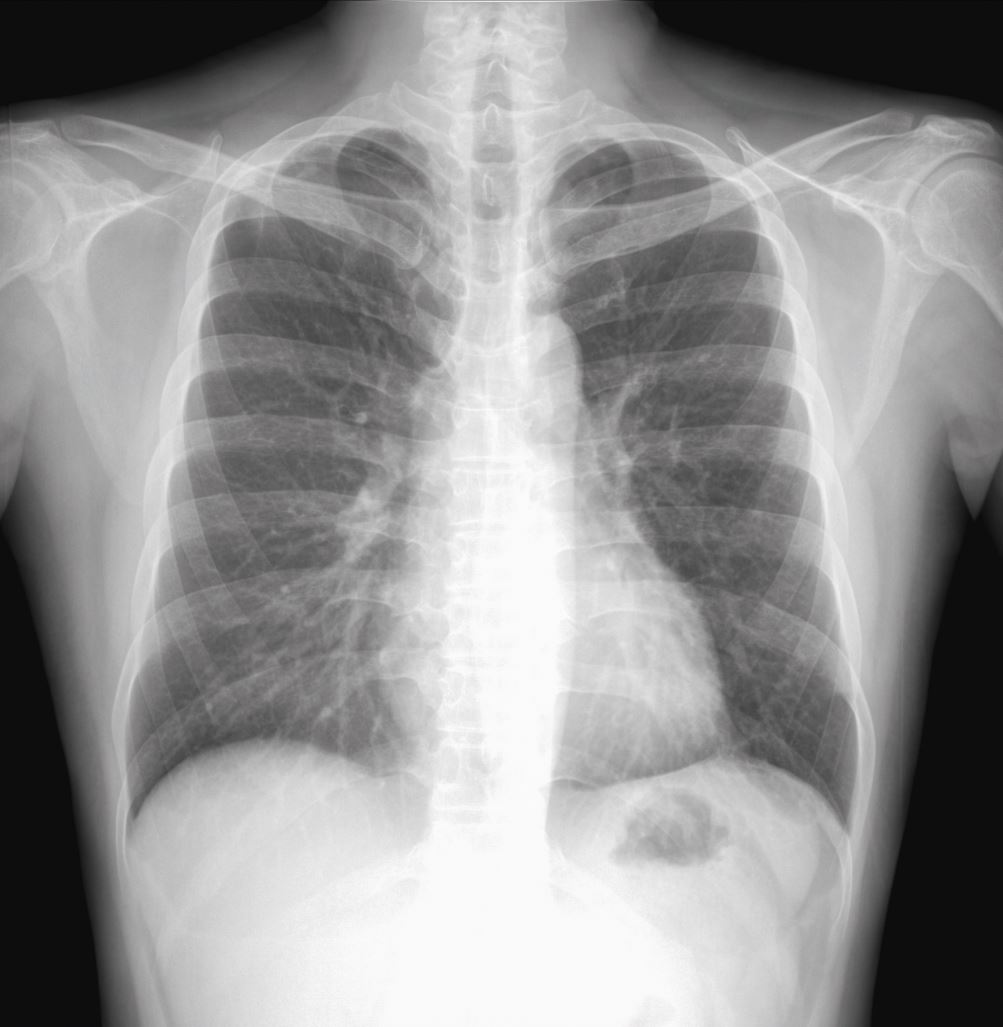

Hintergrund+Fragestellung: Etwa 10.000 Pneumothoraxe werden pro Jahr in Deutschland behandelt. Klinisch wird bei den Spontanpneumothoraces zwischen dem primären und sekundären Spontanpneumothorax (PSP und SSP) unterschieden, die jeweils ein unterschiedliches Management erfordern. Im Therapiealgorithmus der AWMF bzw. den beteiligten Fachgesellschaften wird bei einem kleinen, sich nicht spontan resorbierenden bzw. einem großen Pneumothorax entweder eine Luftaspiration oder die Anlage einer Thoraxdrainage (≤ 14 Chr) empfohlen, wobei unklar bleibt, wann konkret welches Vorgehen zu bevorzugen sei [1]. Die British Thoracic Society empfiehlt dagegen primär die Luftaspiration, die American College of Chest Physicians wiederum ab einem Pneumothoraxvolumen von > 20 % die Anlage einer Thoraxdrainage [2, 3, 4, 5]. Ziel der hier vorgestellten prospektiven Studie ist angesichts des fehlenden internationalen Konsensus die Klärung dieses Aspekts bei Nichtrisikopatienten mit einem ersten Spontanpneumothorax.

Bei Nichtrisikopatienten mit einem ersten Spontanpneumothorax kann die pleurale Luftaspiration als sicheres und gegenüber der Thoraxdrainage besser verträgliches Therapieverfahren gelten.